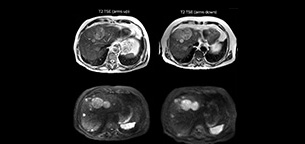

Dr. Kukuk scans an increasing number of liver patients in an arms-up position using the integrated Posterior coil and a special positioning device. “By placing the patient’s arms up, the field of view in the right-left direction can be smaller so that a right-left preparation direction can be used to cut down the scan time,” he explains. “We can use high dS SENSE factors for TSE imaging, so we can shorten the echo train length. This results in a faster scan than arms-down T2 TSE and the images show high anatomical detail.”

“For DWI, the high dS SENSE factor allows using a shorter TE so we get higher signal and fewer susceptibility artifacts, which means less distortion of diffusion weighted images. Of course, with higher dS SENSE factors and the shortening of the TSE factor in T2-weighted imaging, we can drastically cut down the complete examination time. So, with arms-up we get faster images, less distortion in DWI and less blurring on T2-weighted images. Almost all patients tolerate the arms-up scanning well.”